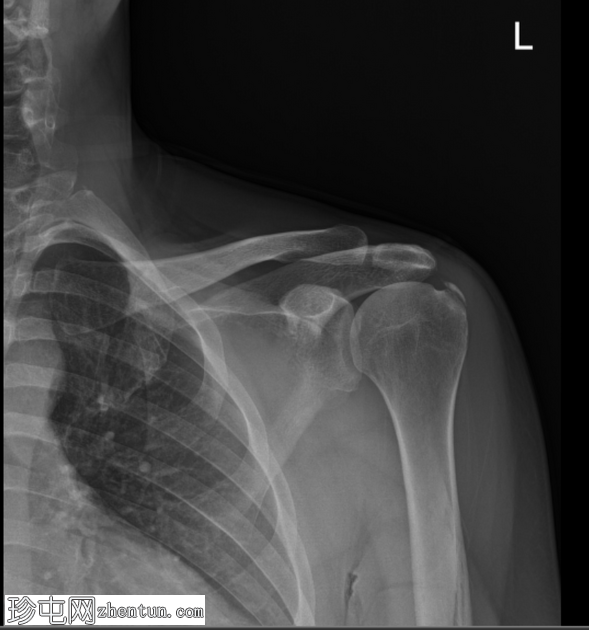

冈上肌腱钙化性肌腱炎

X线片

正位

冈上肌腱止点处可见弧形钙化,符合钙化性肌腱炎的影像学表现

未见相关骨骼异常